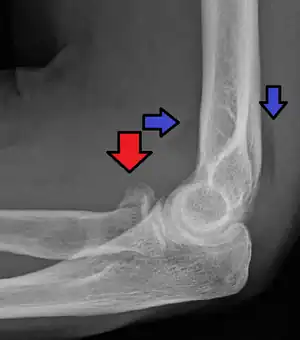

| Radial head fracture (red arrow) with posterior and anterior sail sign (blue arrows) | |

Radial head fractures are diagnosed from an assessment and diagnostic imaging. Assessment may include pain or tenderness at the radial head, bruising, swelling, and a limited range of motion of the elbow.[7] Diagnostic imaging may include ultrasound, plain X-ray, CT scan, and magnetic resonance imaging (MRI).[7][8] A fat pad sign may be present on diagnostic imaging and may indicate a radial head fracture.[9]